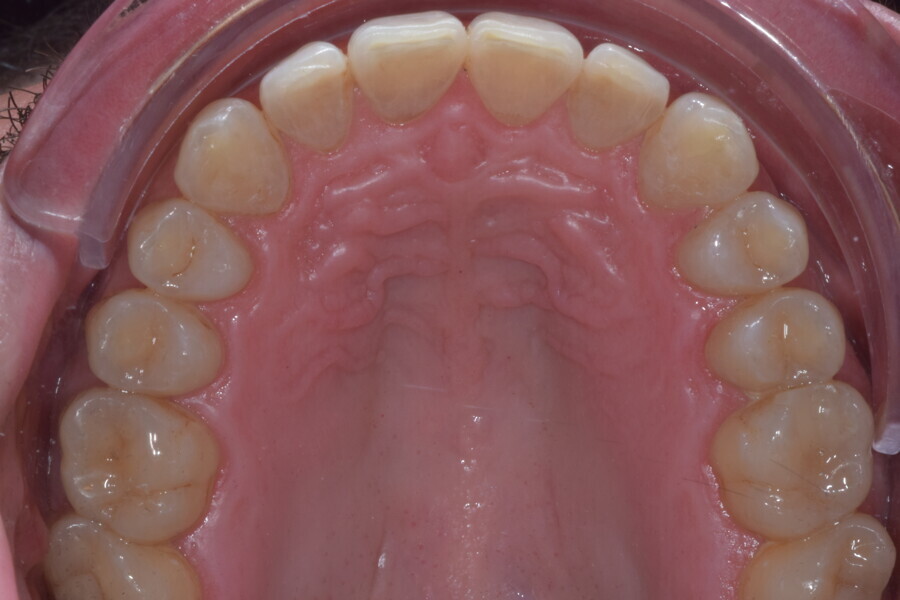

Le motif principal de consultation de ce patient âgé de 37 ans, était de rétablir l’alignement des dents antérieures sur les deux arcades. L’analyse faciale a indiqué une face courte avec un profil plat, mais une projection normale du menton (Figs. 9–12), et l’examen clinique a révélé une classe squelettique de type I (angle ANB = 0,89°) et une malocclusion de classe I avec supraclusion sévère (près de 100 %), une courbe de Spee très prononcée, un torque normal de l’incisive centrale supérieure (Ui-FH = 110°), un encombrement dentaire léger sur l’arcade maxillaire et modéré sur l’arcade mandibulaire (Figs. 13–18). Chez ce patient, les composantes de la supraclusion correspondaient à une dysmorphie squelettique grave correspondant à une hypodivergence (FMA = 14,24°), avec une inclinaison normale des incisives supérieures et inférieures et un angle goniaque réduit (110,46°). L’analyse du cliché céphalométrique indiquait une hauteur réduite de l’étage inférieur de la face associée à l’hypodivergence (Fig. 19). La seule option de traitement envisagée était un traitement orthodontique par aligneurs avec tous les éléments auxiliaires décrits (rampes d’occlusion, zones de pression, nivellement de la courbe de Spee dans les trois dimensions, élastiques de classe II et puissants contacts occlusaux) afin de corriger la supraclusion.

Le plan de traitement numérique (ClinCheck) avait prévu douze aligneurs pour l’arcade maxillaire et dix-sept pour l’arcade mandibulaire. Les objectifs du traitement visaient à combiner les mouvements verticaux d’extrusion des dents postérieures et les mouvements d’intrusion des dents antérieurs, au moyen de rampes d’occlusion, tout en utilisant des taquets d’extrusion pour assurer la désocclusion des dents postérieures et l’intrusion des dents antérieures inférieures, nécessaires au nivellement de l’arcade mandibulaire. La courbe de Spee a été nivelée et le profil plat ainsi que la position des lèvres ont été améliorés par une vestibulo-version des incisives supérieures et inférieures. Le plan avait prévu des élastiques de classe II pour faciliter la vestibulo-version des dents inférieures et les puissants contacts occlusaux postérieurs, avec une extrusion relative des dents postérieures. Une morphologie plus large de l’arcade et une intercuspidation idéale ont été obtenues par des mouvements de torque proches de 0° des dents latérales et postérieures supérieures. Aucune conception technique excessive n’avait été prévue dans le plan de traitement numérique. En raison de l’âge du patient, les aligneurs ont été changés tous les dix jours, dans le cadre d’un traitement d’une durée inférieure à six mois. À la fin de la première série d’aligneurs (Figs. 20–24), un nouveau plan de traitement numérique comportant cinq autres aligneurs a été conçu, en vue d’améliorer l’intercuspidation des molaires sans élastiques. La durée totale du traitement a donc été prolongée jusqu’à 7,5 mois puisque les aligneurs supplémentaires étaient changés toutes les semaines.

À la fin du traitement, on pouvait observer une relation de classe I des canines et des molaires, une légère augmentation de l’inclinaison des incisives supérieures (Ui-FH = 112°), une correction complète de l’inclinaison des incisives inférieures (IMPA = 97,09°) grâce à la vestibulo-version, et une légère amélioration de l’hypodivergence (SN-GoGn = 27°) résultant de l’extrusion relative des dents postérieures, et de l’utilisation d’élastiques de classe II — petite variation (1°) très intéressante compte tenu de l’âge du patient (Figs. 25–35). La ligne du sourire était harmonieuse et correspondait à une relation idéale entre les incisives supérieures et la lèvre inférieure. Le sourire avait été élargi grâce au contrôle du torque des segments latéraux et postérieurs.